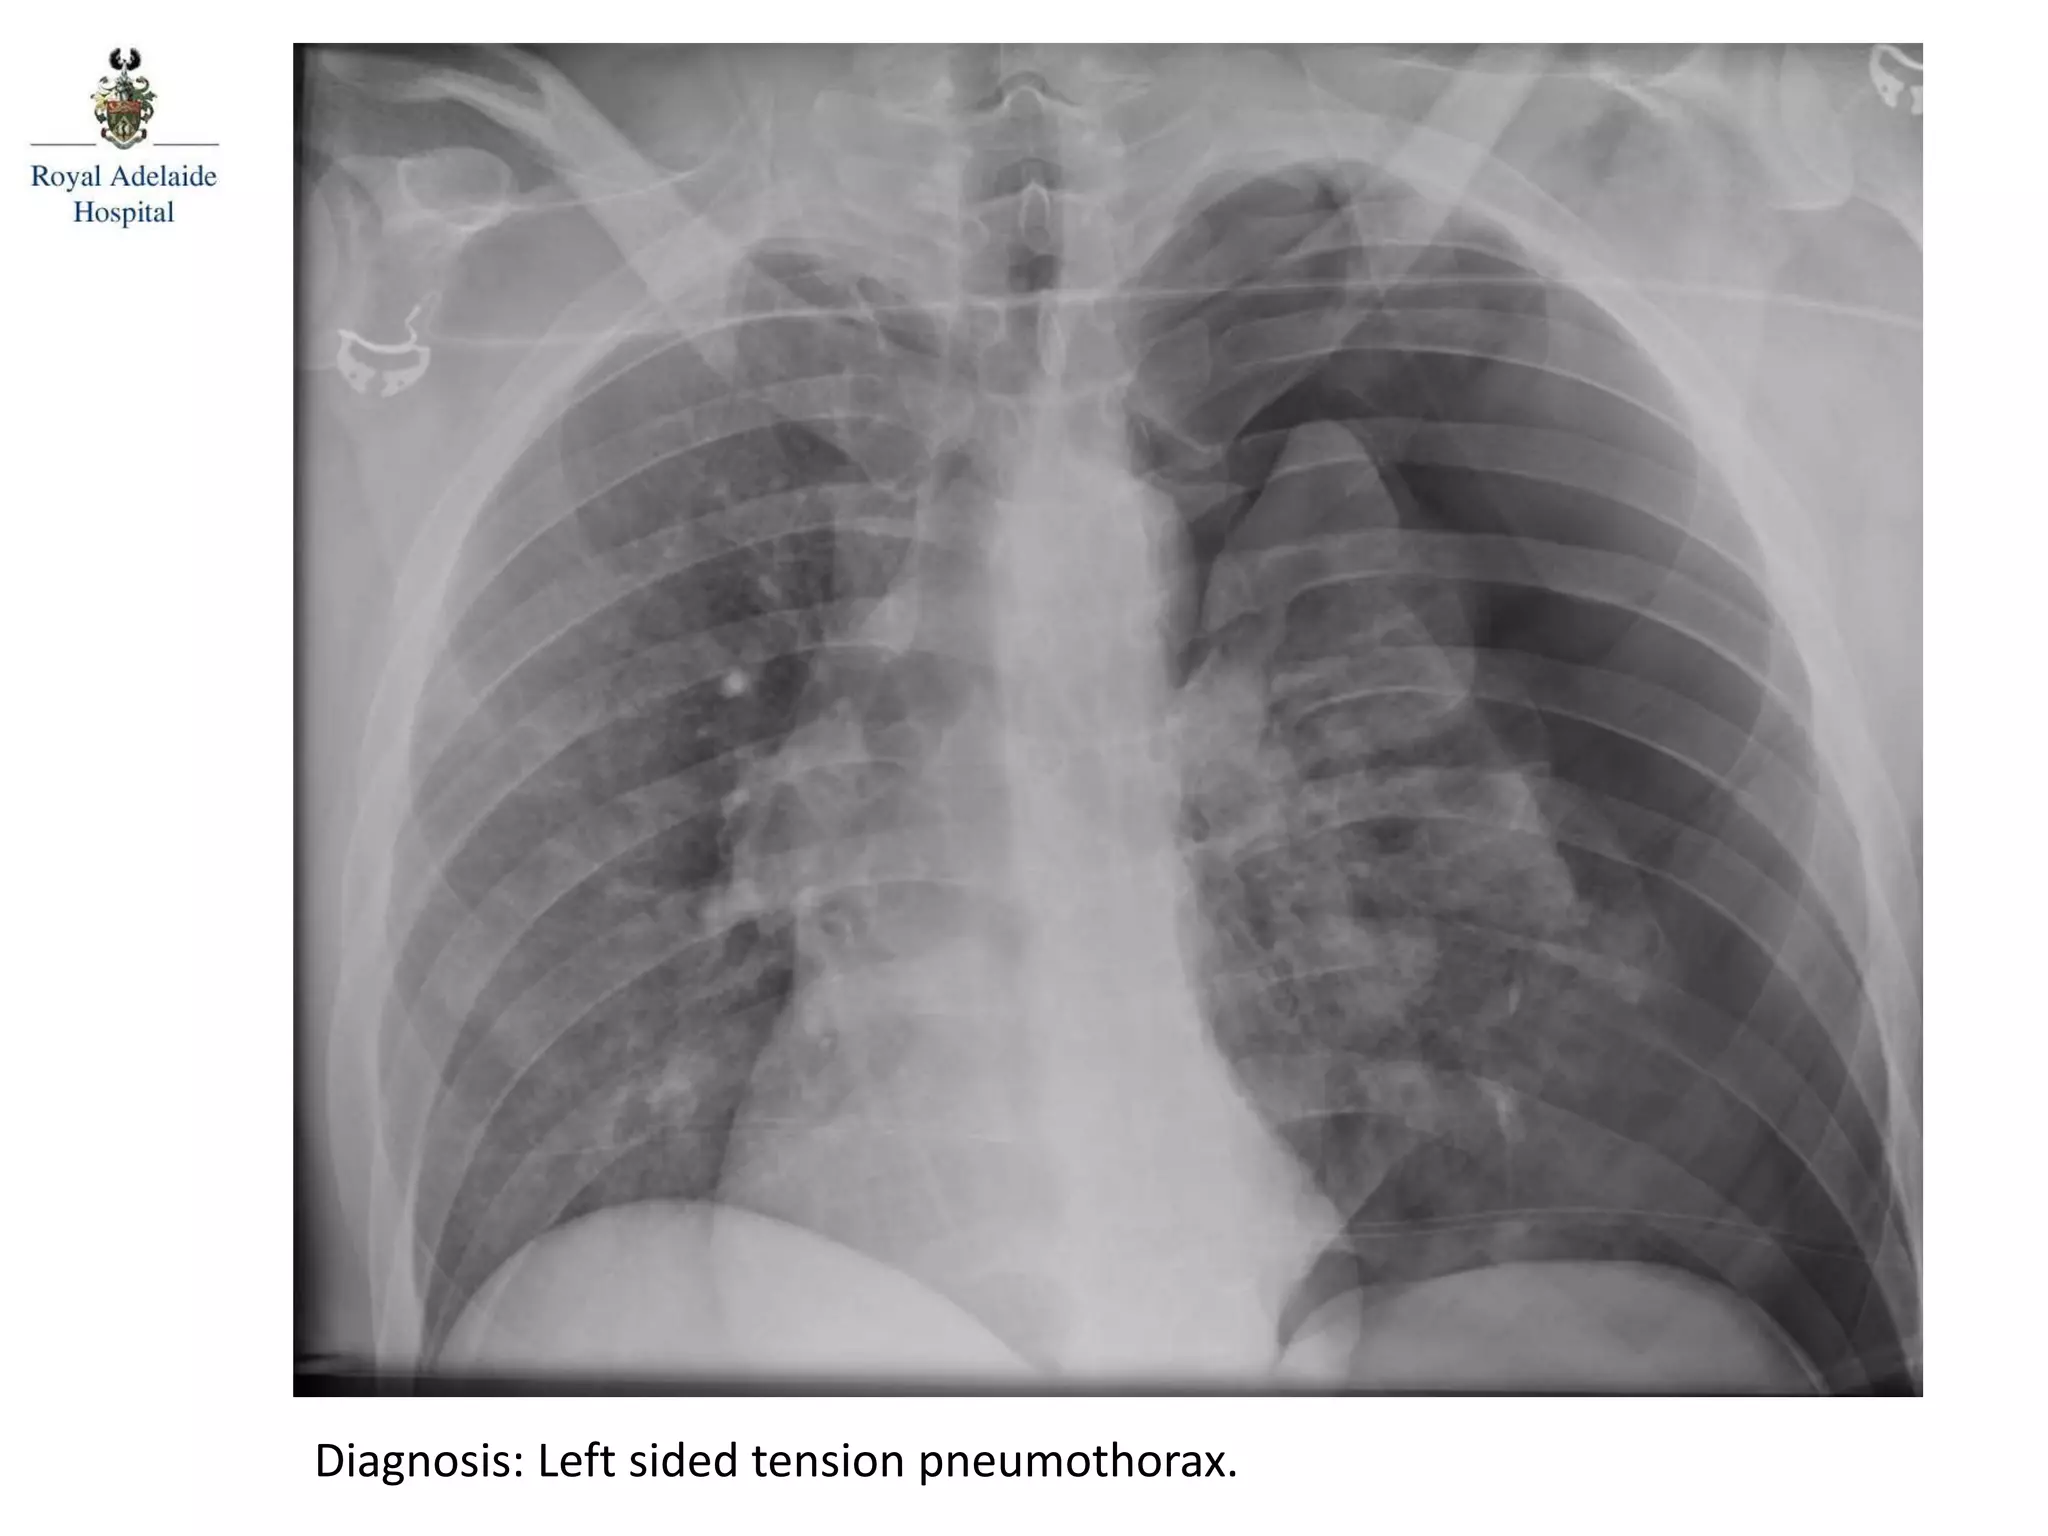

Diagnosis: Left sided tension pneumothorax.